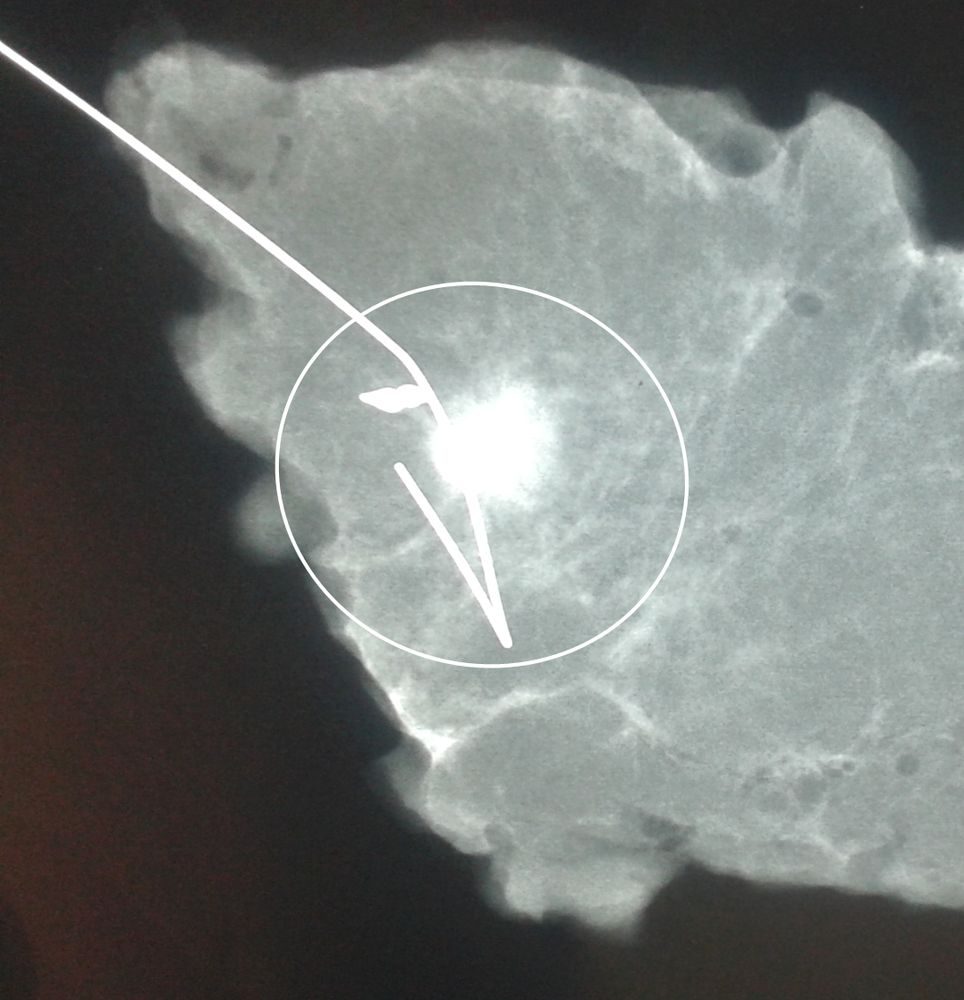

Σε περίπτωση που απαιτείται η χειρουργική αφαίρεση ενός ευρήματος που δε ψηλαφάται από το χειρουργό, τότε γίνεται η τοποθέτηση αγκίστρου σήμανσης (hook) λίγο πριν το χειρουργείο. Το άγκιστρο έχει σκοπό να καθοδηγήσει το χειρουργό για την αφαίρεση του σωστού τμήματος του μαστού, ώστε να αφαιρεθεί με ασφάλεια η ύποπτη βλάβη χωρίς να επηρεασθεί η αισθητική εικόνα του μαστού, πράγμα πολύ σπουδαίο ειδικά σε νέες γυναίκες και σε γυναίκες με μικρό μαστό.